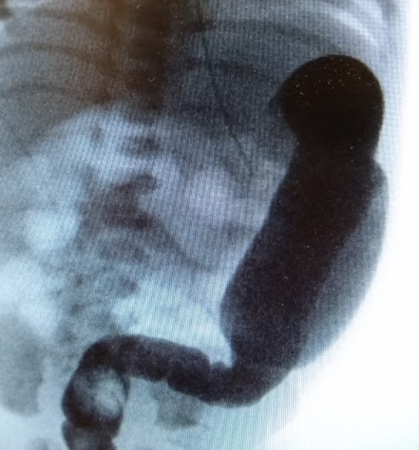

A contrast enema performed with water-soluble contrast material is the most valuable imaging test for Hirschsprung's disease. A contrast enema is recommended if the clinical evaluation is suspicious for Hirschsprung's disease or if there are signs of distal obstruction on x-ray. A rectosigmoid ratio (maximum diameter of the rectum divided by maximum diameter of the sigmoid colon during contrast enema) of <1 is highly suggestive of Hirschsprung's disease. Other suggestive findings include retained contrast at >24 hours, mucosal irregularity, or microcolon.[48] A transition zone may be seen on contrast enema but this may be less obvious in neonates.[49] A transition zone on contrast enema can help with surgical planning, but it should be noted that the radiographic transition zone may not correlate with the histological transition zone.[50] Contrast enema may demonstrate mucosal irregularity in the aganglionic distal colon and may show a transition zone between smaller calibre aganglionic distal colon and dilated proximal ganglionic colon.[Figure caption and citation for the preceding image starts]: Barium enema performed in a newborn with Hirschsprung's disease. Often, classical changes are not obvious in the neonatal periodCorman ML. Colon and rectal surgery. 5th ed. Philadelphia, PA: Lippincott Williams and Wilkins; 2005:555-603; used with permission [Citation ends].